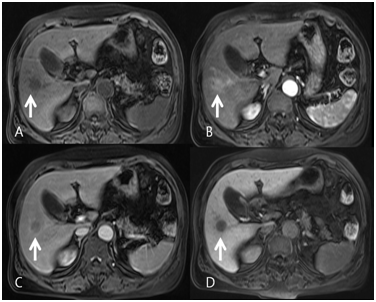

A 72-year-old woman was incidentally found to have a 2.2cm solitary tumor in the right inferior segments on computed tomography (CT). The patient had undergone endoscopic retrograde cholangiopancreraticography (ERCP) one year prior for treatment of cholangitis due to common bile ducts stones. Several gallbladder stones were identified. Cholecystectomy was recommended at that time, but the patient deferred surgery. A liver mass was subsequently identified on follow-up CT, in addition to several gallstones. The patient was asymptomatic. She had no history of alcohol abuse or hepatitis B or hepatitis C viral infection. Blood cell counts and liver enzymes were unremarkable. Alpha fetoprotein (AFP), carbohydrate antigen 19-9 (CA19-9) and carcinoembryonic antigen (CEA) were also within their normal reference ranges. On contrast-enhanced CT scan (non-dynamic CT), the lesion in the S5/6 segment demonstrated heterogeneous enhancement and was described as cholangiocellular carcinoma (Figure 1). Liver magnetic resonance image (MRI) revealed a T1 hypointensity and T2 hyperintensity round well-defined mass. This mass was slightly enhanced in the arterial phase and subsequently washed-out in the portal phase (Figure 2). Hepatocellular carcinoma was highly suspected based on these MRI findings.

Figure 2 Liver magnetic resonance image (MRI). (A) Round low signal mass in precontrast image was slightly enhanced in the arterial phase (B) and subsequently washed-out in the portal phase (C). The mass shows a defect on the 20 minute delay phase of primovist (D). Hepatocellular carcinoma was highly suspected based on these MRI findings.